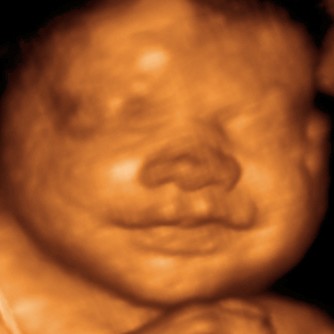

Diagnostic ultrasound, also called sonography or diagnostic medical sonography, is an imaging technique that uses excessive-frequency sound waves to supply photos of structures inside your body. One of the most frequent uses of ultrasound is throughout being pregnant, to observe the growth and improvement of the fetus, however there are many other makes use of, together with imaging the heart, blood vessels, eyes, thyroid, brain, breast, belly organs, skin, and muscular tissues.

An ultrasound machine makes use of excessive frequency sound waves and their resulting echoes to assist decide the scale, shape and depth of an abnormality. It can also be used for minimally invasive surgery to guide the surgeon with actual-time images of the within of the physique. Ultrasonic photos, also called sonograms, are made by sending pulses of ultrasound into tissue utilizing a probe The ultrasound pulses echo off tissues with different reflection properties and are recorded and displayed as an image.

Its intention is commonly to discover a supply of a disease or to exclude pathology The apply of analyzing pregnant girls using ultrasound is named obstetric ultrasound , and was an early growth and application of scientific ultrasonography. When the machine was wheeled in, I pulled the window shades closed and applied the ultrasound probe to his chest.